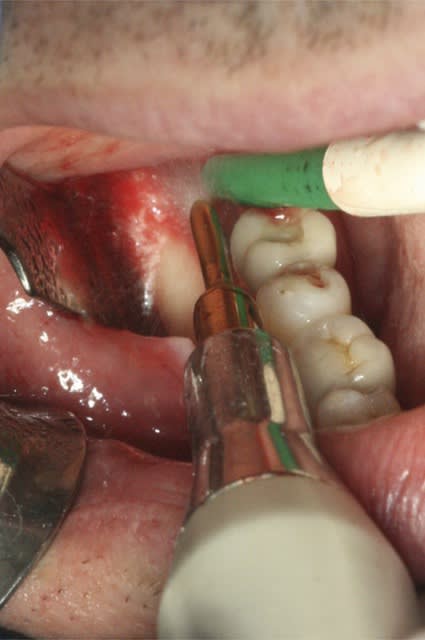

image1: incision verticale + décollement du lambeau de proche en proche

image 5: broyât osseux

image 6: insertion du "toit"

image 7: fixation ( vis Stoma)

image8: ajout du broyât

image 9: sutures

image 12 et 13: réouverture, forage et pose des implants ( les implants ont été posés par le DR A. L dans le 31)